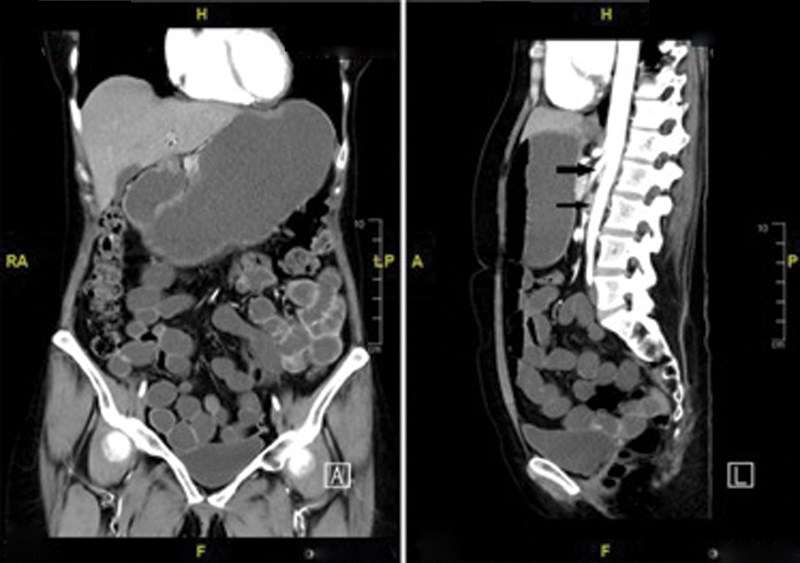

Superior mesenteric artery syndrome is a rare cause of intestinal obstruction. The condition results from compression of the duodenum between the aorta and the superior mesenteric artery, which causes an impairment of gastric emptying and associated chronic symptoms. There is a need to objectively assess the severity of gastric-emptying disorder in these patients post-treatment to assess the efficacy of the conservative or surgical management. We report here a case of a patient where the radionuclide gastric-emptying study was crucial in monitoring the effectiveness of surgical management of this syndrome.